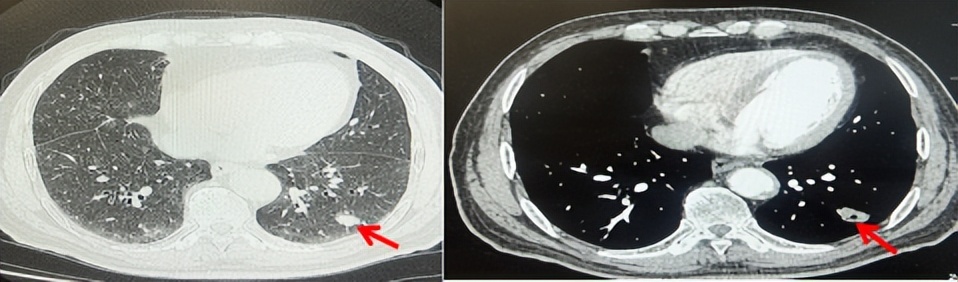

2024.09.12复查胸部CT示左侧胸膜结节,大者约为27mmx13mm,考虑转移可能性大,纵隔淋巴结增大,恶性?(如图6)。患者行胸膜穿刺活检取病理,结果示(胸膜)结合免疫组化,支持鳞状细胞癌,PD-L1(克隆号28-8)TPS约20%。分期为rT0N2bM1a IVA期,DFS为10个月。2024.09.24起行替雷利珠单抗联合紫杉醇+卡铂方案治疗4周期,复查胸CT评效SD(如图7)。后患者因脑梗塞停止治疗,于综合医院就诊,后未返院复查及治疗。

图7:替雷利珠单抗联合白蛋白紫杉醇+卡铂治疗4周期后(2024.12)胸部CT肺窗及纵隔窗